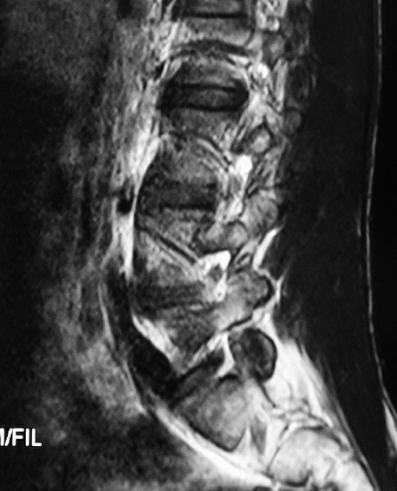

CT显示L4/5节段的椎间盘突出脱垂型(图1)。MRI示L4/5节段的椎间盘突出到Ⅲ层面(图2)。红外热成像显示左侧下肢的皮温明显低于右侧(图3)。

图2 MRI L4~5节段矢状位片:椎间盘脱垂到Ⅲ层面

MRI矢状位片:神经根在椎间孔的位置正常(图7)。

图7 MRI矢状位L4神经根在椎间孔的位置正常